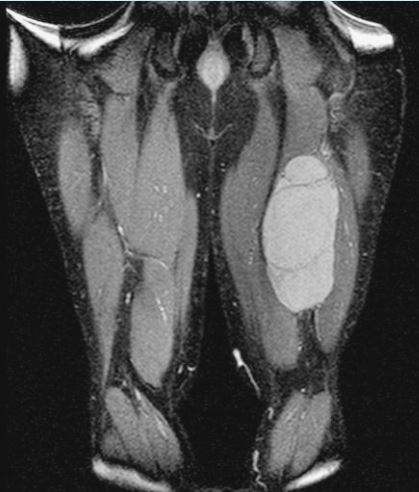

This is an MRI of the hamstrings tumor. The tumor is the brightened part on the right hand side of the thigh in the image seen.